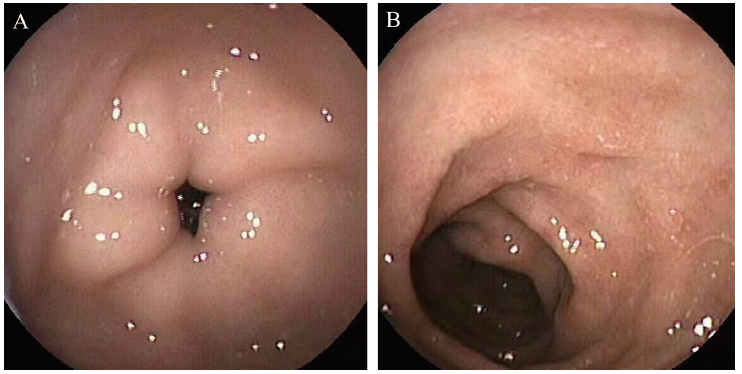

血常规示白细胞 12.71×109 /L,中性粒细胞5.52×109/L,EOS 1.3 %,AEC 0.17×109/L,红细胞2.21×1012/L,血红蛋白 70 g/L,血小板 638×109/L,CRP 207.6 mg/L;ESR 44 mm/h。总蛋白 54.7 g/L,白蛋白 31.0 g/L,血钠136 mmol/L,二氧化碳结合力 12.6 mmol/L。IgG 7.2 g/L,IgA 0.86 g/L,IgM 0.43 g/L;总IgE 143 IU/mL,sIgE阳性。大便常规白细胞40 ~ 50个/高倍视野,大便隐血(+),未见真菌孢子及寄生虫;期间3次大便培养未见沙门菌属和志贺菌属。血培养:普通培养5 d未见细菌生长。流式细胞免疫功能检测CD3+增高(78.7%),CD3+CD4+下降(19.7%)、CD16+56+下降(8.9%),CD3+CD8+、CD19+正常。X线胸片未见异常,腹部立位片示肠管充气欠均匀,部分扩张,中下腹可见少许浅小液平;腹部B超示部分肠管积气明显,未见肠套叠声像图。胃镜示十二指肠球部黏膜肿胀,结肠镜(富士)示乙状结肠、降结肠黏膜散在浅凹溃疡灶(图1);病理示胃窦黏膜固有层内少量淋巴细胞和嗜酸性粒细胞(0 ~ 3个/高倍视野)浸润,降结肠、乙状结肠浅表黏膜活动性炎。

图1 例2 FPIES患儿胃镜图

注:A为胃窦正常黏膜;B为十二指肠球部糜烂。